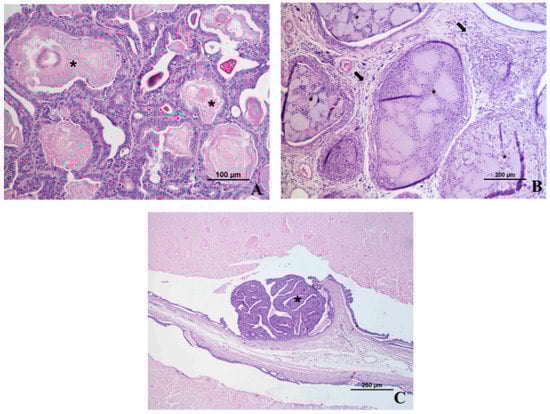

4. Microscopic Anatomy